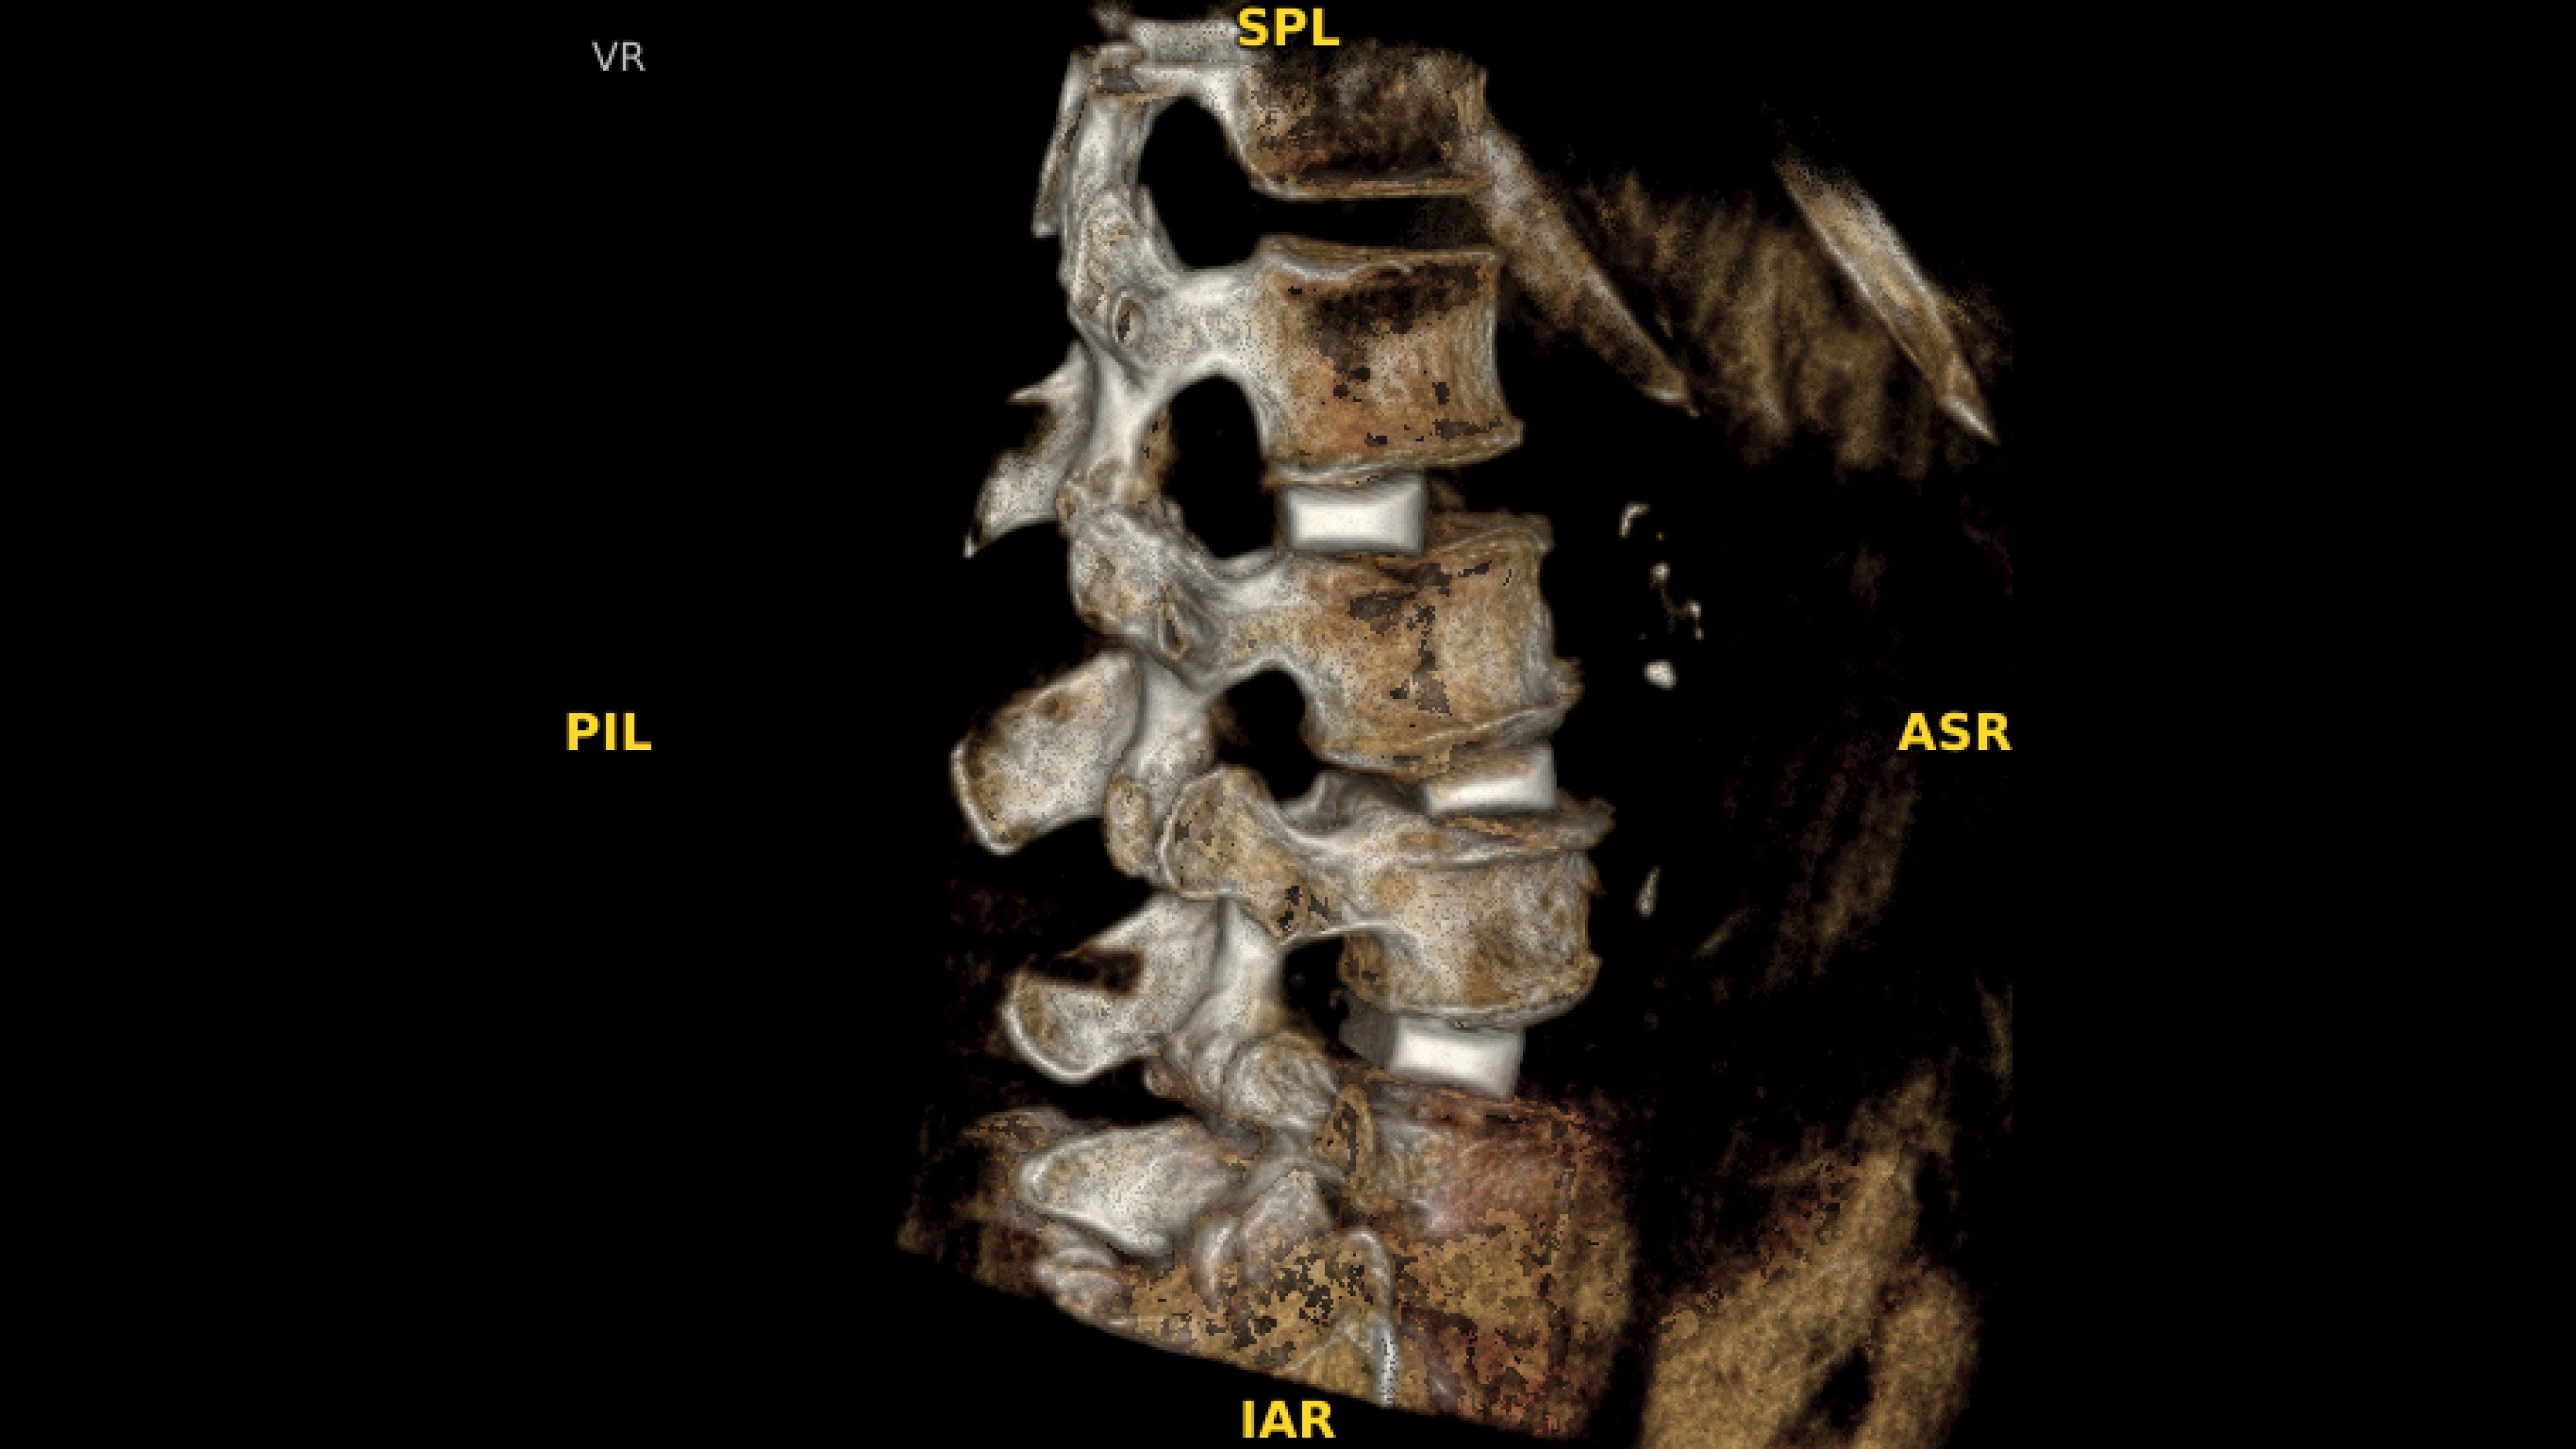

With OEC 3D, comprehensive imaging coverage of 19 cm x 19 cm x 19 cm 3D volumes and exceptional 2D images enables viewing several levels of the spine in the operating room.

The OEC 3D presents five perspectives: Axial, Coronal, Sagittal, MIP, and VR, on a 4K display for clear and detailed review of 3D volumes and 2D images